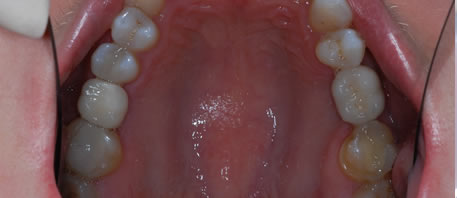

Before Dental Implant

dental implants northern ireland

After Dental Implant